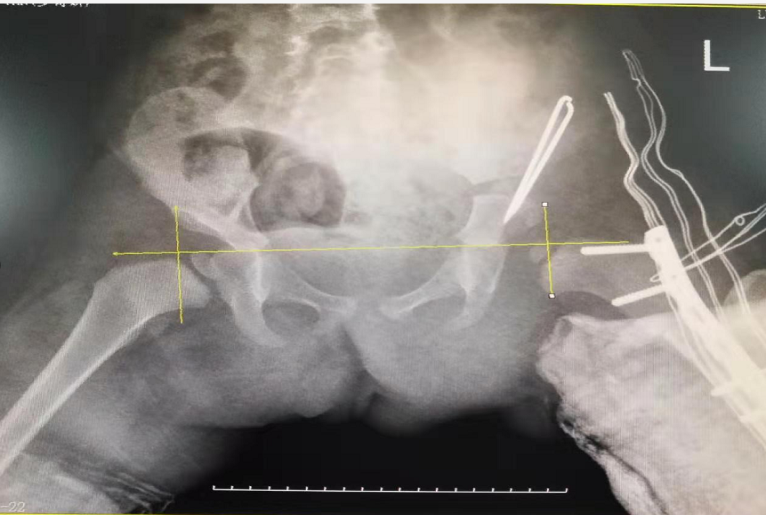

术前

术后